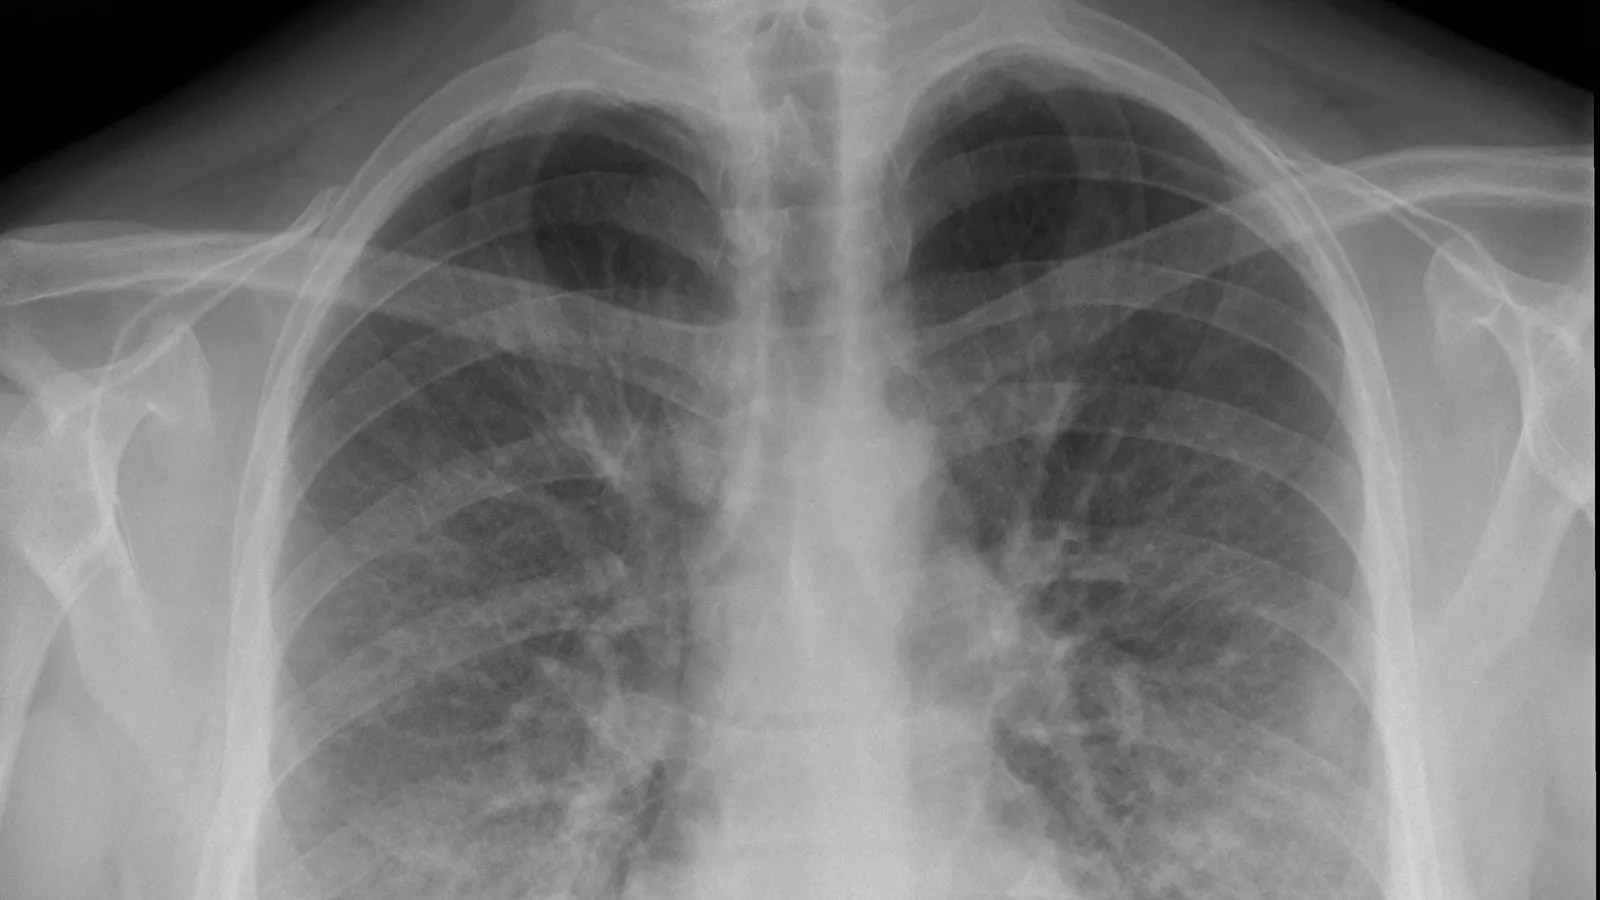

How To Know If You Have Evali . Healthy lungs are filled with air and appear dark. What are the signs and symptoms of evali? Rough criteria for patients with probable evali: Recent history of vaping (especially concerning if using thc oils or adulterated vape liquids). To be classified as evali, cases have to satisfy the following criteria: The following can happen suddenly or get worse. Having vaped or “dabbed” (inhaled a concentrated cannabis product) in the 90 days before symptoms started You may feel like you have the flu at first. Evali is considered in patients who have vaped or dabbed within 90 days of symptom onset, and have abnormal lung imaging in the absence of any.